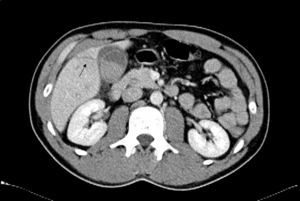

Se trata de un varón de 30 años sin antecedentes de interés que acude al servicio de urgencias por agresión con arma blanca en abdomen. A su llegada el paciente está estable con TA 121/72, FC 50 y presenta únicamente una herida incisa de 1cm en hipocondrio derecho. No hay dolor abdominal espontáneo ni a la palpación en abdomen y el Murphy es negativo. La analítica al ingreso no muestra alteraciones y se realiza TAC abdominal en el que se observa una laceración hepática que alcanza el lecho de la vesícula, la cual presenta un coágulo en su interior y mínimo líquido libre alrededor (fig. 1). Dado el buen estado general del paciente y la ausencia de clínica se decide tratamiento conservador e ingreso en reanimación para monitorización. A las 24h el paciente permanece estable hemodinámicamente y sin dolor abdominal. Se repite la analítica encontrando como único hallazgo una alteración del perfil hepático (Bilirrubina total 2,8mg/dl, GPT 536U/L, GOT 555U/L) y se decide esperar. A las 48h la bioquímica mejora espontáneamente (bilirrubina total 1,4mg/dl, GPT 357U/L, GOT 162U/L) y se comprueba ecográficamente la desaparición del líquido libre perivesicular y ausencia de dilatación de la vía biliar. No aparece en ningún momento dolor abdominal, ictericia ni cuadro de melenas o hematemesis, por lo que el paciente es trasladado a planta y se inicia tolerancia oral. Al cuarto día es dado de alta asintomático con hemograma y bioquímica normales. En la revisión posterior al mes el paciente persiste sin síntomas y 8 meses después se confirma telefónicamente que permanece asintomático y desestima seguimiento.